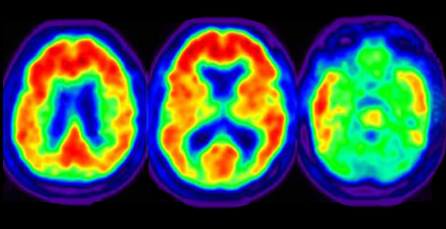

What Uses Do Gamma Rays Have. Introduce a gamma-emitting radioisotope into body attached to a biologically interesting molecule and observe how it distributes through different organs. Gamma-ray imaging in medicine.

Diagnostic nuclear medicine Functional imaging shows how organs are working not just their structure physiology not just. Gamma radiation can kill living organisms including bacteria. X-rays may penetrate the human body but are absorbed by the more bone-like parts of.

As production of radioisotopes and. The radioactivity is converted to electrical impulses by the camera and the information is passed to a computer which produces an image on a TV screen. Routine therapeutic applications of gamma rays in teletherapy and brachytherapy but also modern techniques as gamma-knife radiosurgery are presented.